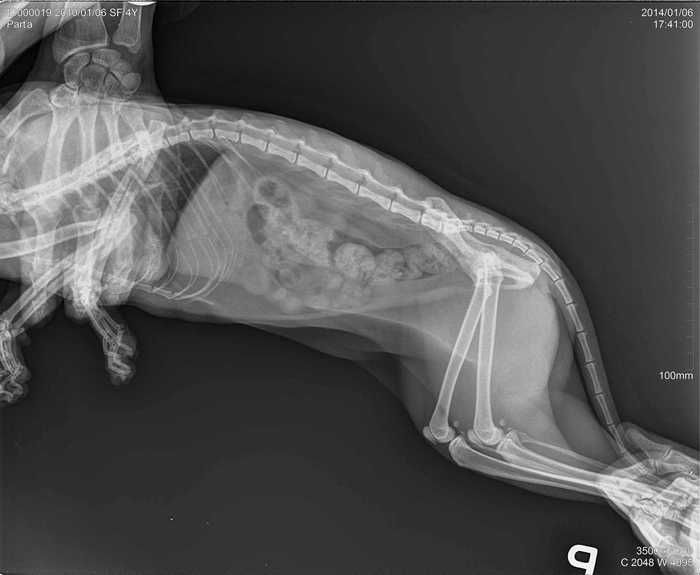

Úvod > Galerie > RTG snímky